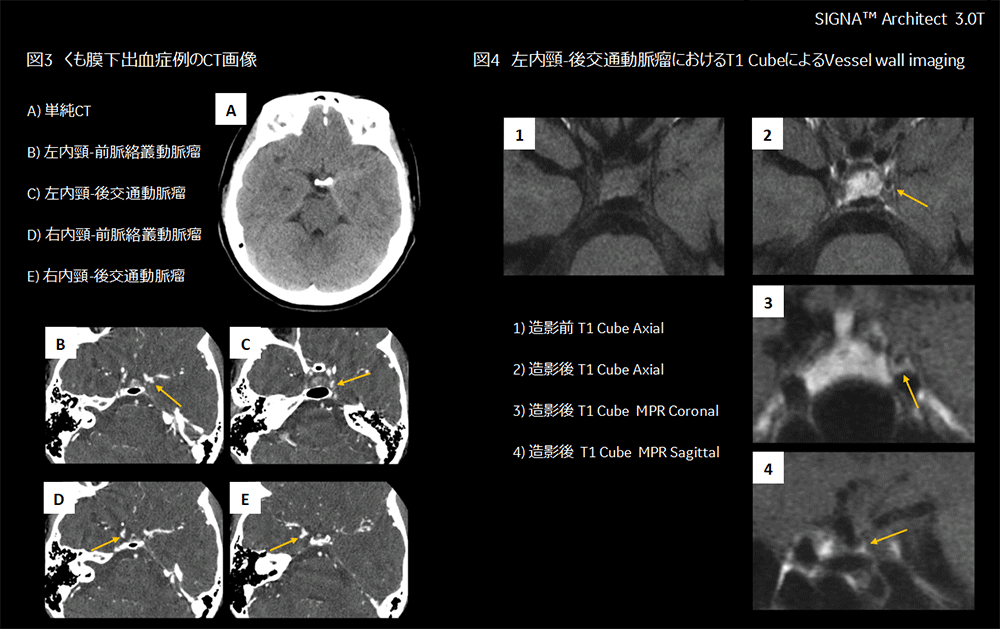

40代女性。1週間前より後頭部痛があり受診。頭部CT検査よりSAHと診断され、左内頸-前脈絡叢動脈、左内頸-後交通動脈、右内頸-前脈絡叢動脈、右内頸-後交通動脈に動脈瘤が認められた(図3)。左の動脈瘤の破裂が疑われたが、破裂動脈瘤を同定するために翌日3.0T装置にて、造影剤投与前後でT1 Cubeを用いたVessel wall imagingを撮像した。

(T1 Cube撮像条件:FOV200×140mm、Matrix400×400、slice thickness/interval 0.4mm/0mm、TR690ms、TE24ms)

造影MRIにて左内頸-前脈絡叢動脈、右内頸-前脈絡叢動脈、右内頸-後交通動脈の動脈瘤周囲の増強効果は認められなかったが、左内頸-後交通動脈の動脈瘤後面に増強効果が認められたため、左内頸-後交通動脈の動脈瘤破裂によるSAHと診断された(図4)。カテーテル治療にてコイリングを行い、対側は後日手術の方針となった。術後経過は良好で新たな神経症状なく退院された。

Architect_Okazakishimin_05.png